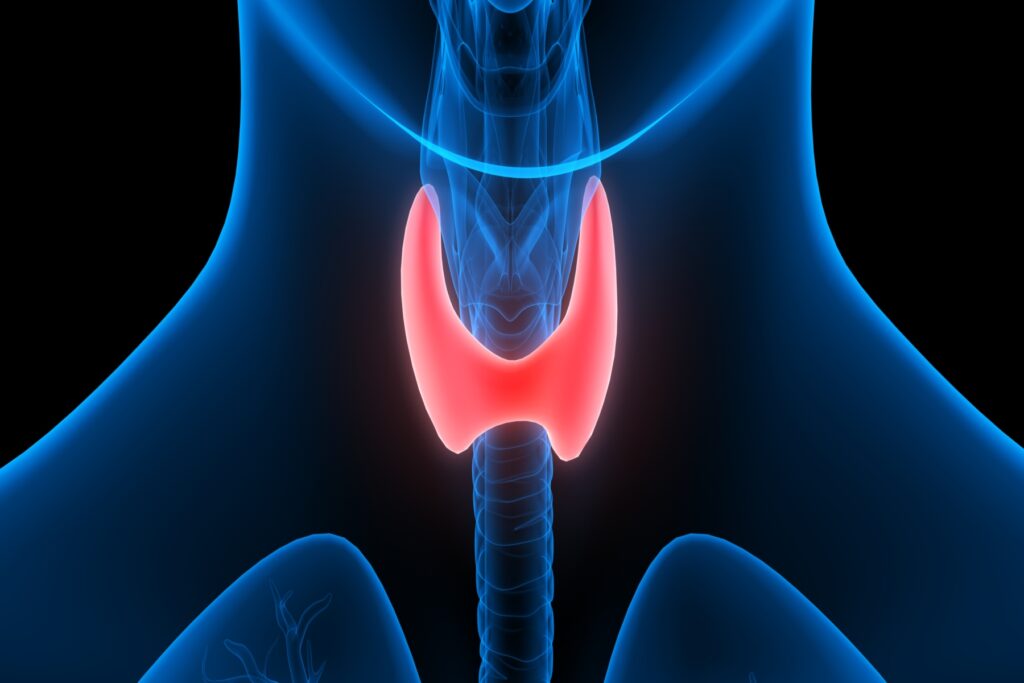

Ο υποθυρεοειδισμός εμφανίζεται όταν ο θυρεοειδής αδένας δεν παράγει αρκετές θυρεοειδικές ορμόνες. Αυτό μπορεί να επιβραδύνει τον μεταβολισμό. Τα συμπτώματα περιλαμβάνουν αίσθημα κόπωσης, αύξηση βάρους και ευαισθησία στο κρύο. «Σε ορισμένες περιπτώσεις, οι διαταραχές του θυρεοειδούς έχουν συσχετιστεί με συμπτώματα άνοιας που μπορεί να είναι αναστρέψιμα με τη θεραπεία», δήλωσε ο συγγραφέας της μελέτης Chien-Hsiang Weng, MD, MPH, του Πανεπιστημίου Brown στο Providence του Ρόουντ Άιλαντ. «Ενώ χρειάζονται περισσότερες μελέτες για να επιβεβαιωθούν αυτά τα ευρήματα, οι άνθρωποι θα πρέπει να γνωρίζουν τα προβλήματα του θυρεοειδούς ως πιθανό παράγοντα κινδύνου για άνοια και θεραπείες που θα μπορούσαν να αποτρέψουν ή να επιβραδύνουν τη μη αναστρέψιμη γνωστική έκπτωση».

Για τη μελέτη, οι ερευνητές εξέτασαν τα αρχεία υγείας 7.843 ατόμων που είχαν πρόσφατα διαγνωστεί με άνοια στην Ταϊβάν και τα συνέκριναν με τον ίδιο αριθμό ατόμων που δεν είχαν άνοια. Ο μέσος όρος ηλικίας τους ήταν τα 75 έτη. Οι ερευνητές έψαξαν να δουν ποιος είχε ιστορικό είτε υποθυρεοειδισμού είτε υπερθυρεοειδισμού και βρήκαν ότι συνολικά 102 άτομα είχαν υποθυρεοειδισμό και 133 είχαν υπερθυρεοειδισμό. Δεν βρήκαν σχέση μεταξύ υπερθυρεοειδισμού και άνοιας.

Από τα άτομα με άνοια, 68 άτομα, ή 0,9%, είχαν υποθυρεοειδισμό (34 από τα άτομα χωρίς άνοια), ή 0,4%. Όταν οι ερευνητές προσάρμοσαν άλλους παράγοντες που θα μπορούσαν να επηρεάσουν τον κίνδυνο άνοιας, όπως το φύλο, η ηλικία, η υψηλή αρτηριακή πίεση και ο διαβήτης, διαπίστωσαν ότι τα άτομα άνω των 65 ετών με υποθυρεοειδισμό είχαν 80% περισσότερες πιθανότητες να αναπτύξουν άνοια από τα άτομα της ίδιας ηλικίας που είχαν προβλήματα με τον θυρεοειδή. Για άτομα κάτω των 65 ετών, το ιστορικό υποθυρεοειδισμού δεν συσχετίστηκε με αυξημένο κίνδυνο άνοιας.